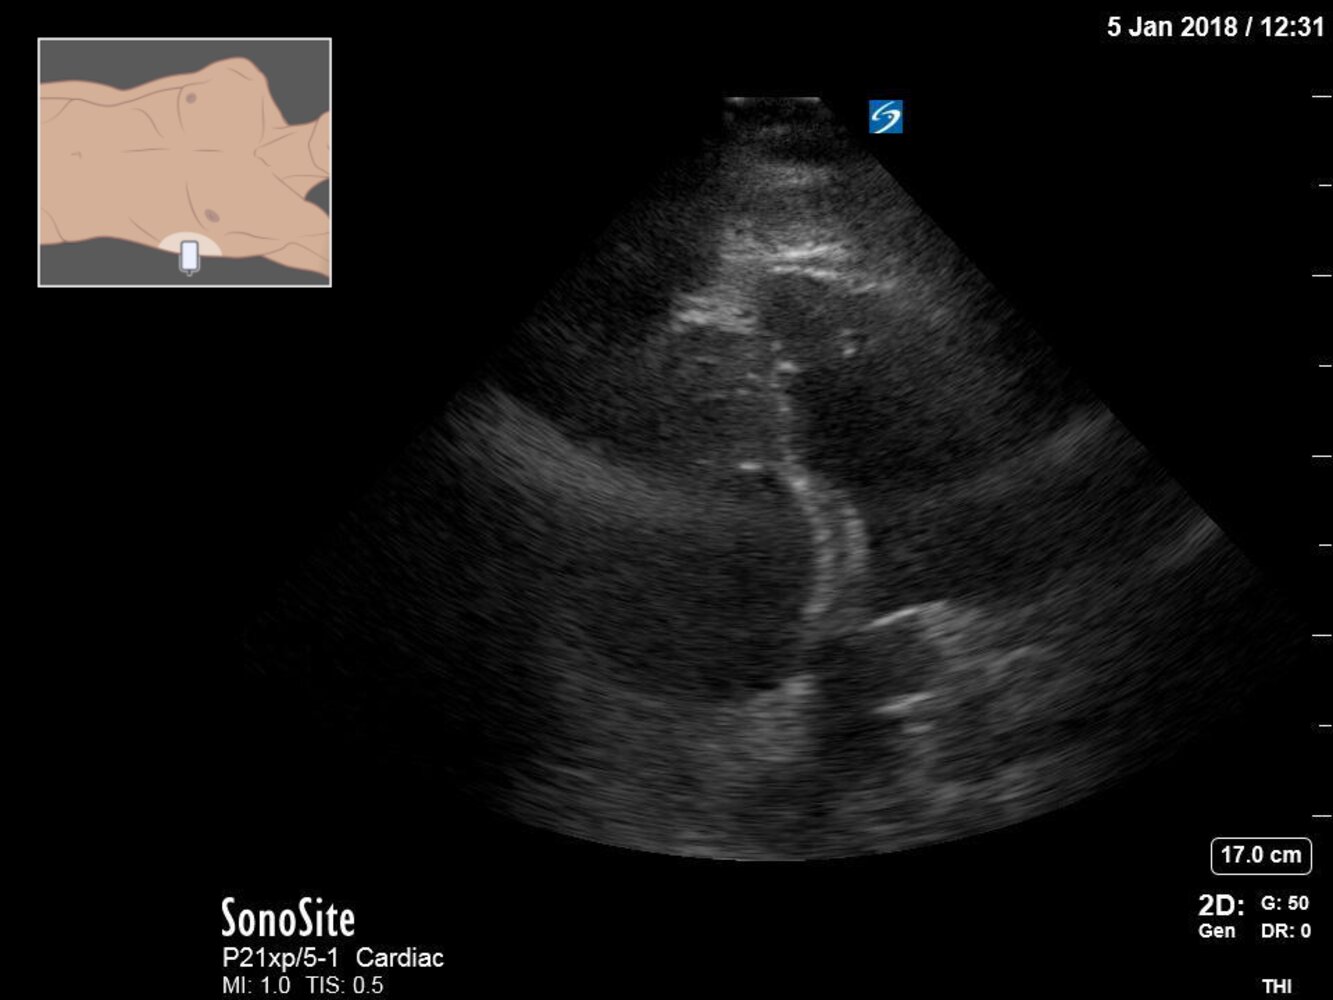

Chest x-ray [7][20]

-

Chest x-ray findings in cardiogenic pulmonary edema

- Enlarged heart shadow due to cardiomegaly and/or pericardial effusion [21]

- Kerley B lines (also known as septal lines)

- Prominent pulmonary vessels and perihilar alveolar edema (the hilar shadow has a butterfly or “bat wing” appearance)

- Basilar interstitialedema

- Bilateral pleural effusions [22]

- Cephalization: increased prominence of pulmonary vessels in the upper lobes of the lungs due to venous congestion [23]

- Peribronchial cuffing

ABCDE: Alveolar edema (bat wings), Kerley B lines (interstitial edema), Cardiomegaly, Dilated prominent pulmonary vessels, and Effusions

POCUS in acute heart failure

Description: bedside ultrasound of the lung fields, inferior vena cava (IVC), and heart

- Can be used to assess volume status prior to and during treatment

- Higher diagnostic accuracy than chest x-ray combined with NT-proBNP [11][27]

- Technique: See “Focused cardiac ultrasound.”

Characteristic findings [28][29][30][31]

Lung fields

- Pleural effusions

- ≥ 3 B lines in ≥ 2 bilateral lung zones suggest pulmonary edema [32]

- IVC ultrasound: diameter ≥ 2–2.5 cm, reduced IVC collapsibility [30]